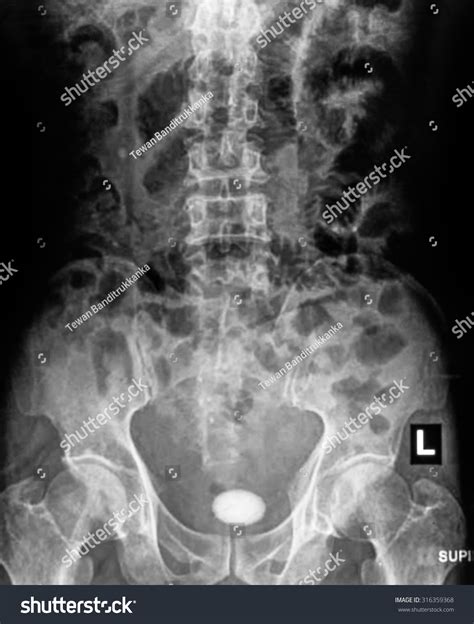

A Kub Abdominal X Ray, also known as a KUB (Kidneys, Ureters, Bladder) X-ray, is a type of abdominal radiograph that provides a detailed view of the abdominal cavity. This imaging technique is commonly used to assess the organs and structures within the abdomen, including the kidneys, ureters, bladder, intestines, and other soft tissues. The primary goal of a Kub Abdominal X Ray is to detect abnormalities such as obstructions, infections, or tumors.

• Calcifications or stones in the kidneys or bladder

Kidney Stones Calcifications in the kidneys that can cause severe pain and urinary tract infections.

Appendicitis Inflammation of the appendix, which can lead to rupture if not treated promptly.